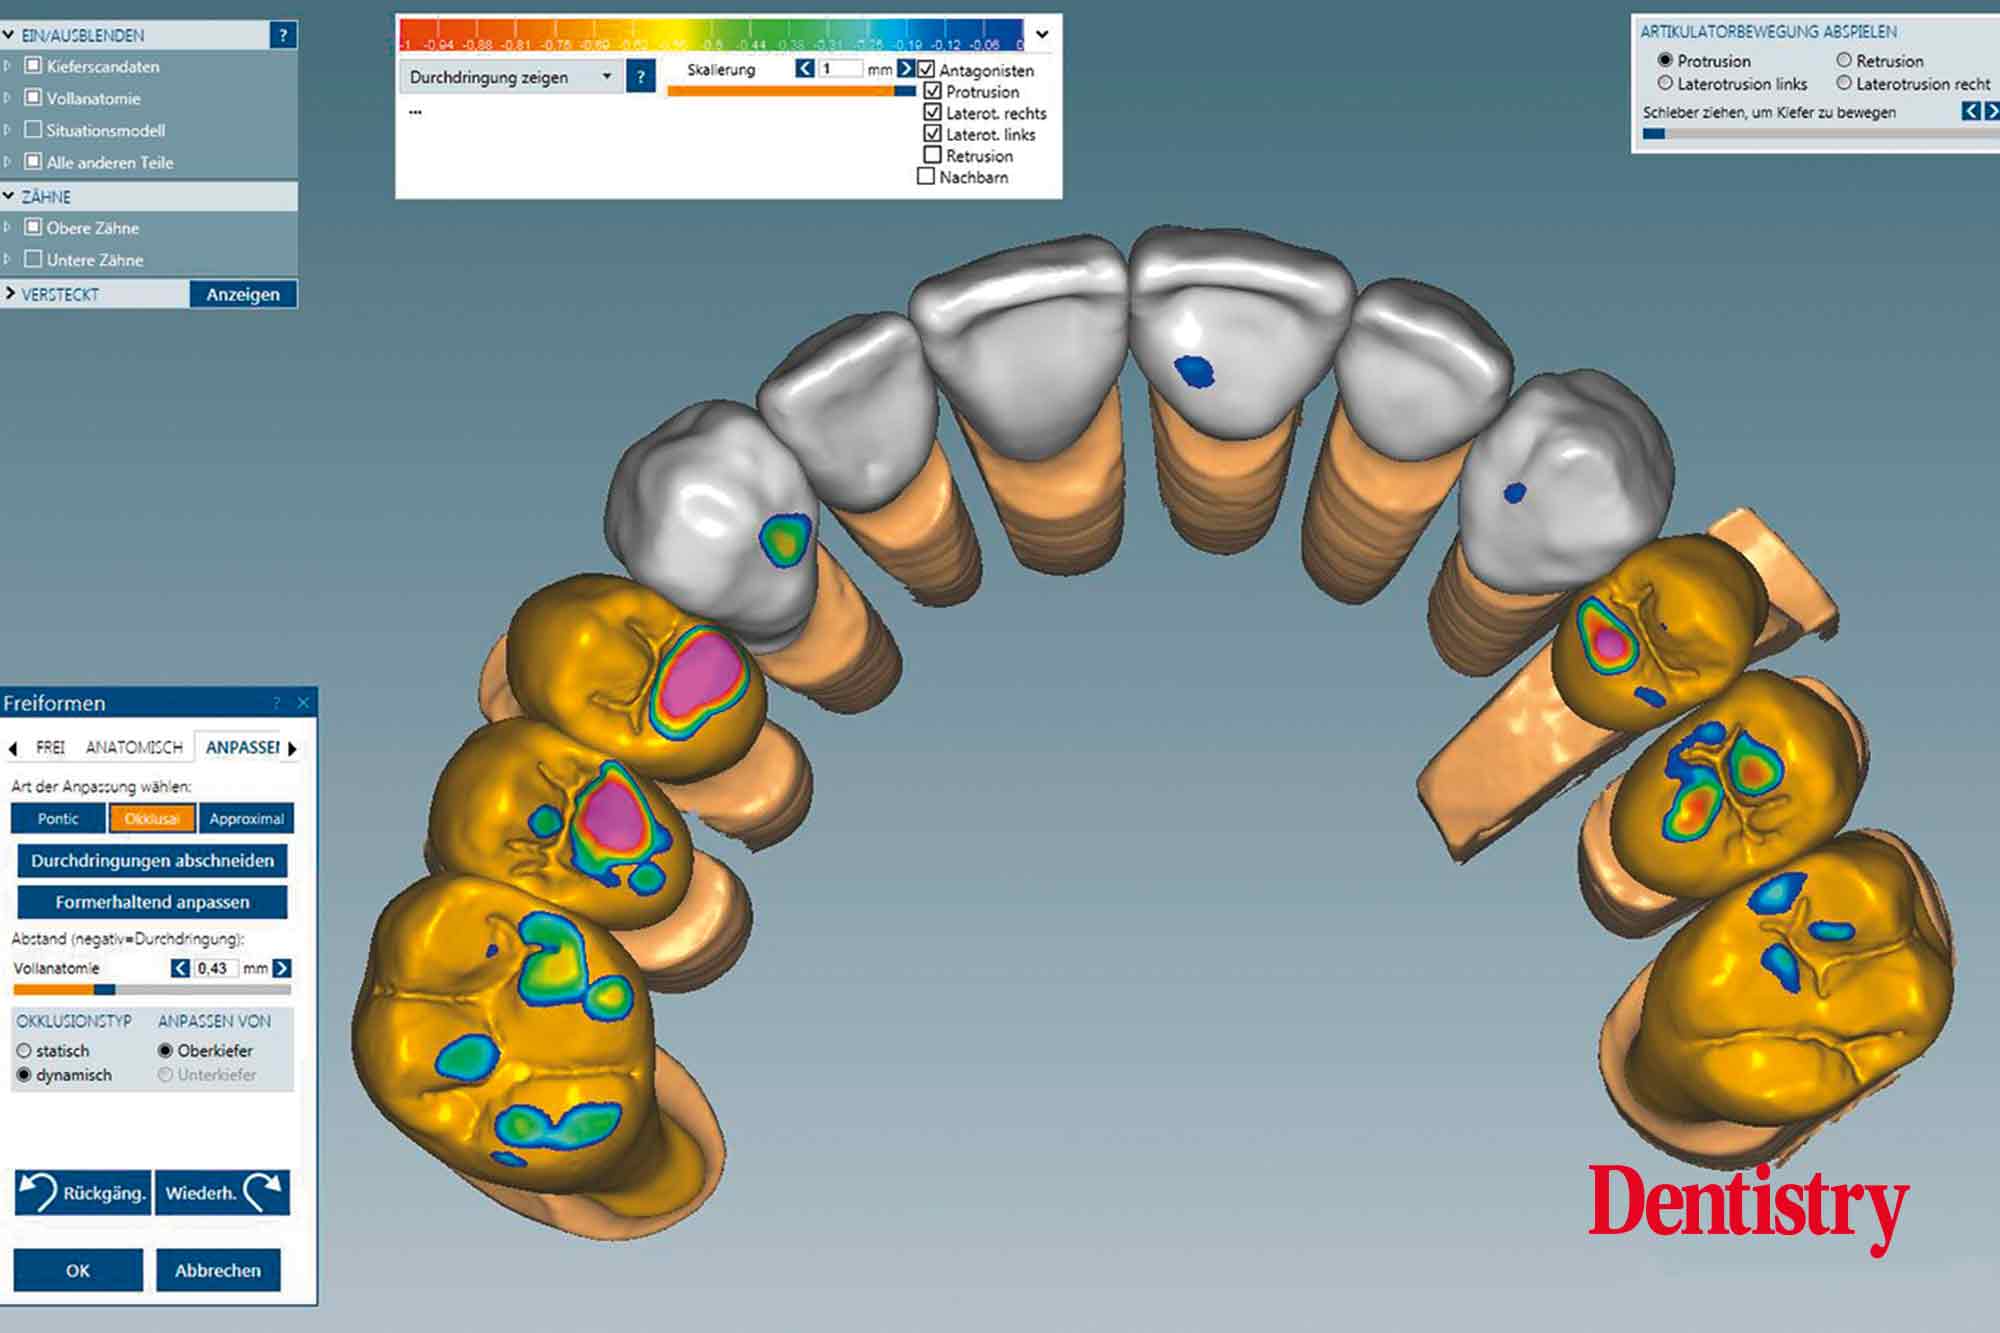

The scanned models were evaluated on a virtual 11 articulator. Temporary Ceramill PMMA (Amann Girrbach) transparent acrylic crowns were CAD planned (Figures 3a to 3d).

Patient data including condylar movements were recorded by the software. Using the Initial situation software’s customised incisal guide unit, the incisal guide pin was adjusted on the splitex plate to the desired cuspal inclinations on the virtual temporary crowns (Figure 4).

All patient parameters including condylar inclination were transferred to the Ceramill Artex articulator and the lateral and protrusive excursions were established while having no contact with the anterior teeth (Figures 5 to 8).